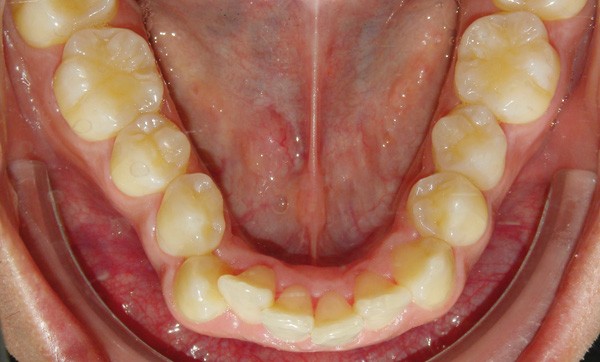

La demande du patient est d’aligner ses dents de l’arcade mandibulaire et de fermer les espaces résiduels d’extraction au maxillaire (fig. 2a à e). Ses fréquents déplacements professionnels à l’étranger, durant chaque fois plusieurs mois, ne lui permettent pas des rendez-vous réguliers au cabinet.

Sur le plan dentaire, dans le sens sagittal, il existe une classe II molaire thérapeutique et une classe I canine avec des espaces résiduels d’extractions en distal des canines chiffrés à 1,5 mm à droite et 2,5 mm à gauche. Les rebords des 11 et 21 ont été fracturés et reconstitués au composite (fig. 2a à e).

À la mandibule, la DDM est chiffrée à 4 mm environ ; 43 est en mésiovestibuloposition et en occlusion en bout à bout avec 12 ; 42 est en linguoposition, 35 en rotation axiale mésiolinguale ; 44 présente une anomalie de forme avec un diamètre mésiodistal augmenté et vestibulolingual diminué (dysharmonie dento-dentaire).